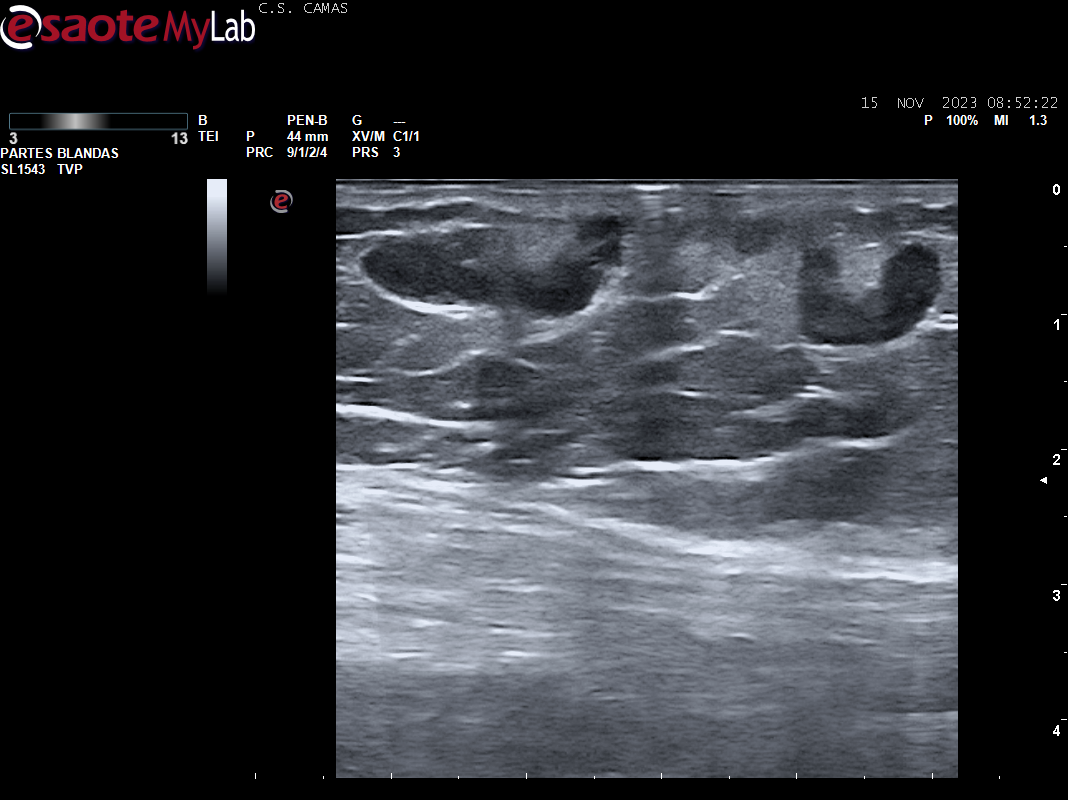

Ecografia vascular cara interna del muslo izq: Trombosis de todo el recorrido de la safena izq con dolor al paso de la sonda por colaterales inferiores que colapsan. Presenta además en zona del cayado de la safena imagen heterogenea sin apreciar la llegada de la safena a la femoral común compatible con arrancamiento de la misma.

Trombosis de todo el recorrido de la safena interna izquierda con tromboflebitis de las colaterales inferiores que concuerda con el diagnóstico hospitalario.